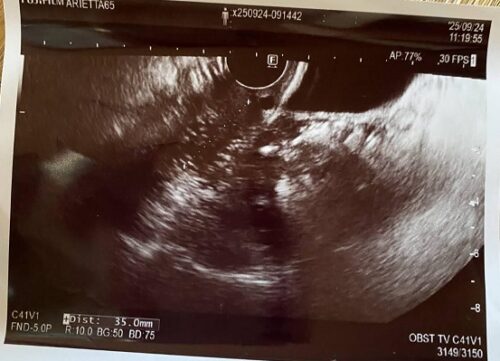

2024年のエコー